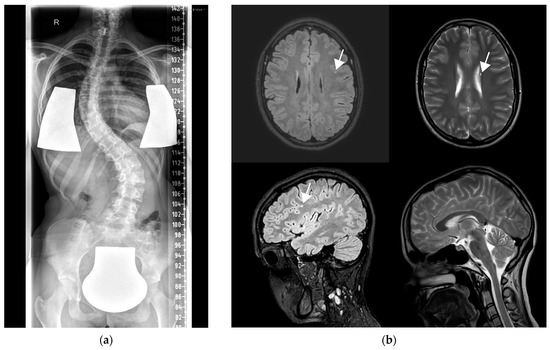

| This study | #43 (15 y) | comp het, c.364G>A (p.Glu122Lys), c.336+1G>A (p.?) | + (12 y) | + (8 y) | + (2 y) | Mild ID |

| #44 (21 y) | hom, c.430G>T (p.Gly144Trp) | + (16 y) | + (13 y) | + (GTCS 12y on urinary tract infection) | Gradual progression of movement disorders into dystonia on recurrent viral infections |